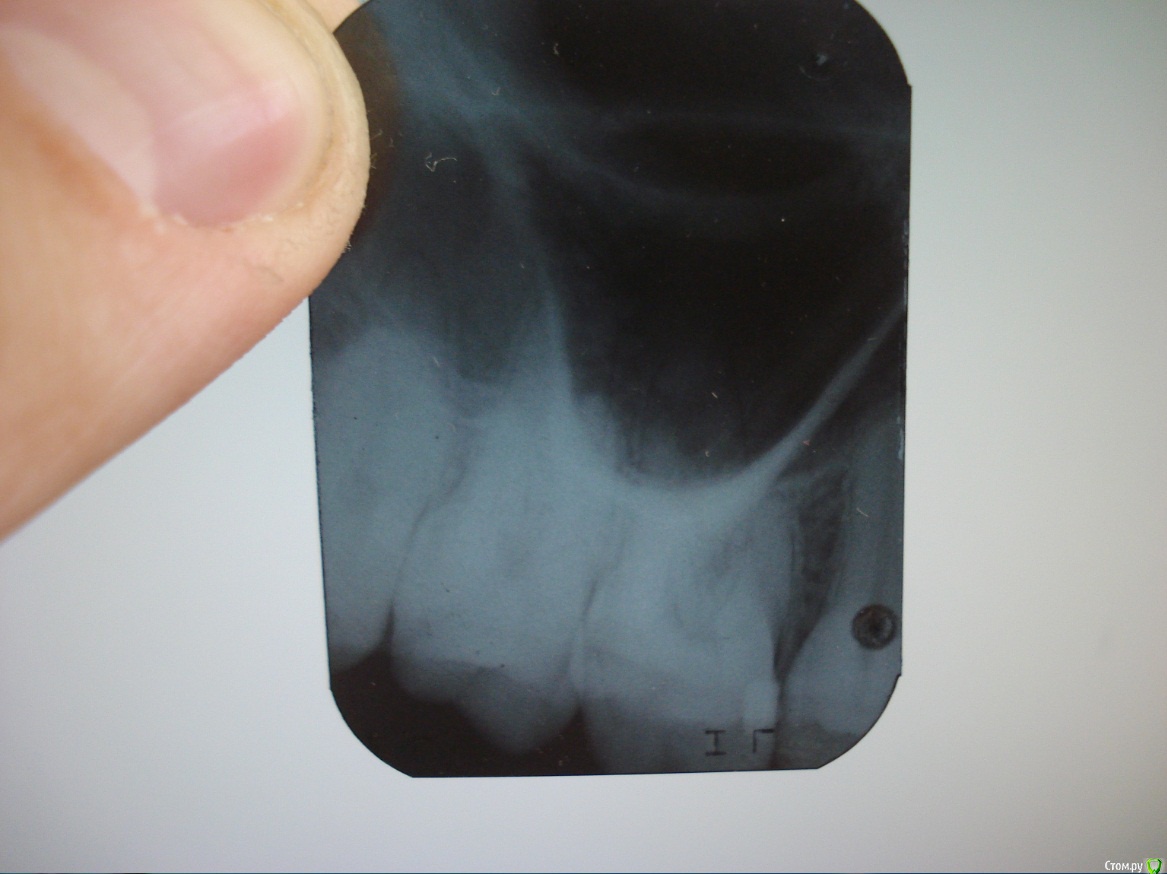

n0nst0p_ Опубликовано 15 июля, 2015 Поделиться Опубликовано 15 июля, 2015 (изменено) Добрый день , уважаемые стоматологи . Хочу попросить у вас совета с постановкой диагноза .Сегодня с утра у меня начал болеть зубчик (16) , запломбированый год назад склоиномером ( 2 клас по Блэку) . Никогда до этого не болел , даже когда был кариес не реагировал ни на сладкое ни на другие раздражители . После пломбирования никаких неприятный ощущений никогда небыло до сегодня . С 9 утра , постоянно , боль почти не проходит , но болит слабо . Где-то 3-4 по шкале боли от 1 до 10 . Боль ноющая , тупая . Реакция на температурные , механические и химические раздражители отсутствует . Перкусия горизонтальная и вертикальная - отрицательные . То , что на рентгенограме прочитать не могу , опыта нету в этом . Иногда были схожие боли , когда просыпается 18 зуб , который в ретинированом состоянии , но тогда боль локализовалась в другом месте , а сейчас в районе 16 зуба . Также болит немного глаз и подочноямковая область(вчера продуло) , что может наводить мысль о невралгии .Если есть вопросы или предположения , можете использовать мед. терминологию , студент 3 курса стомат . факультета. Изменено 15 июля, 2015 пользователем n0nst0p_ Ссылка на комментарий

n0nst0p_ Опубликовано 15 июля, 2015 Автор Поделиться Опубликовано 15 июля, 2015 А вот эта тень на рентген-снимке , это гайморовая пазуха? (извините за глупые вопросы , просто форма странная) . Ссылка на комментарий

red_butler Опубликовано 15 июля, 2015 Поделиться Опубликовано 15 июля, 2015 А вот эта тень на рентген-снимке , это гайморовая пазуха? да Ссылка на комментарий

red_butler Опубликовано 15 июля, 2015 Поделиться Опубликовано 15 июля, 2015 Есть проблемы с краевым прилеганием пломбы и возможно с контактным пунктом. Еда забивается между шестым и пятым? Ссылка на комментарий